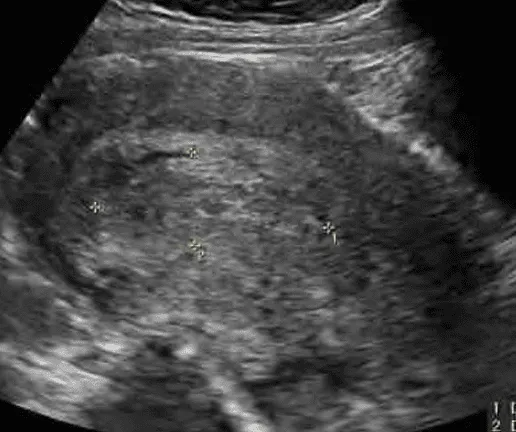

Sảy thai không trọn

Phần tiêu đề “Sảy thai không trọn”Ra huyết rỉ rả, đau quặn bụng, cổ tử cung hé mở, siêu âm thấy khối echo hỗn hợp trong lòng tử cung.